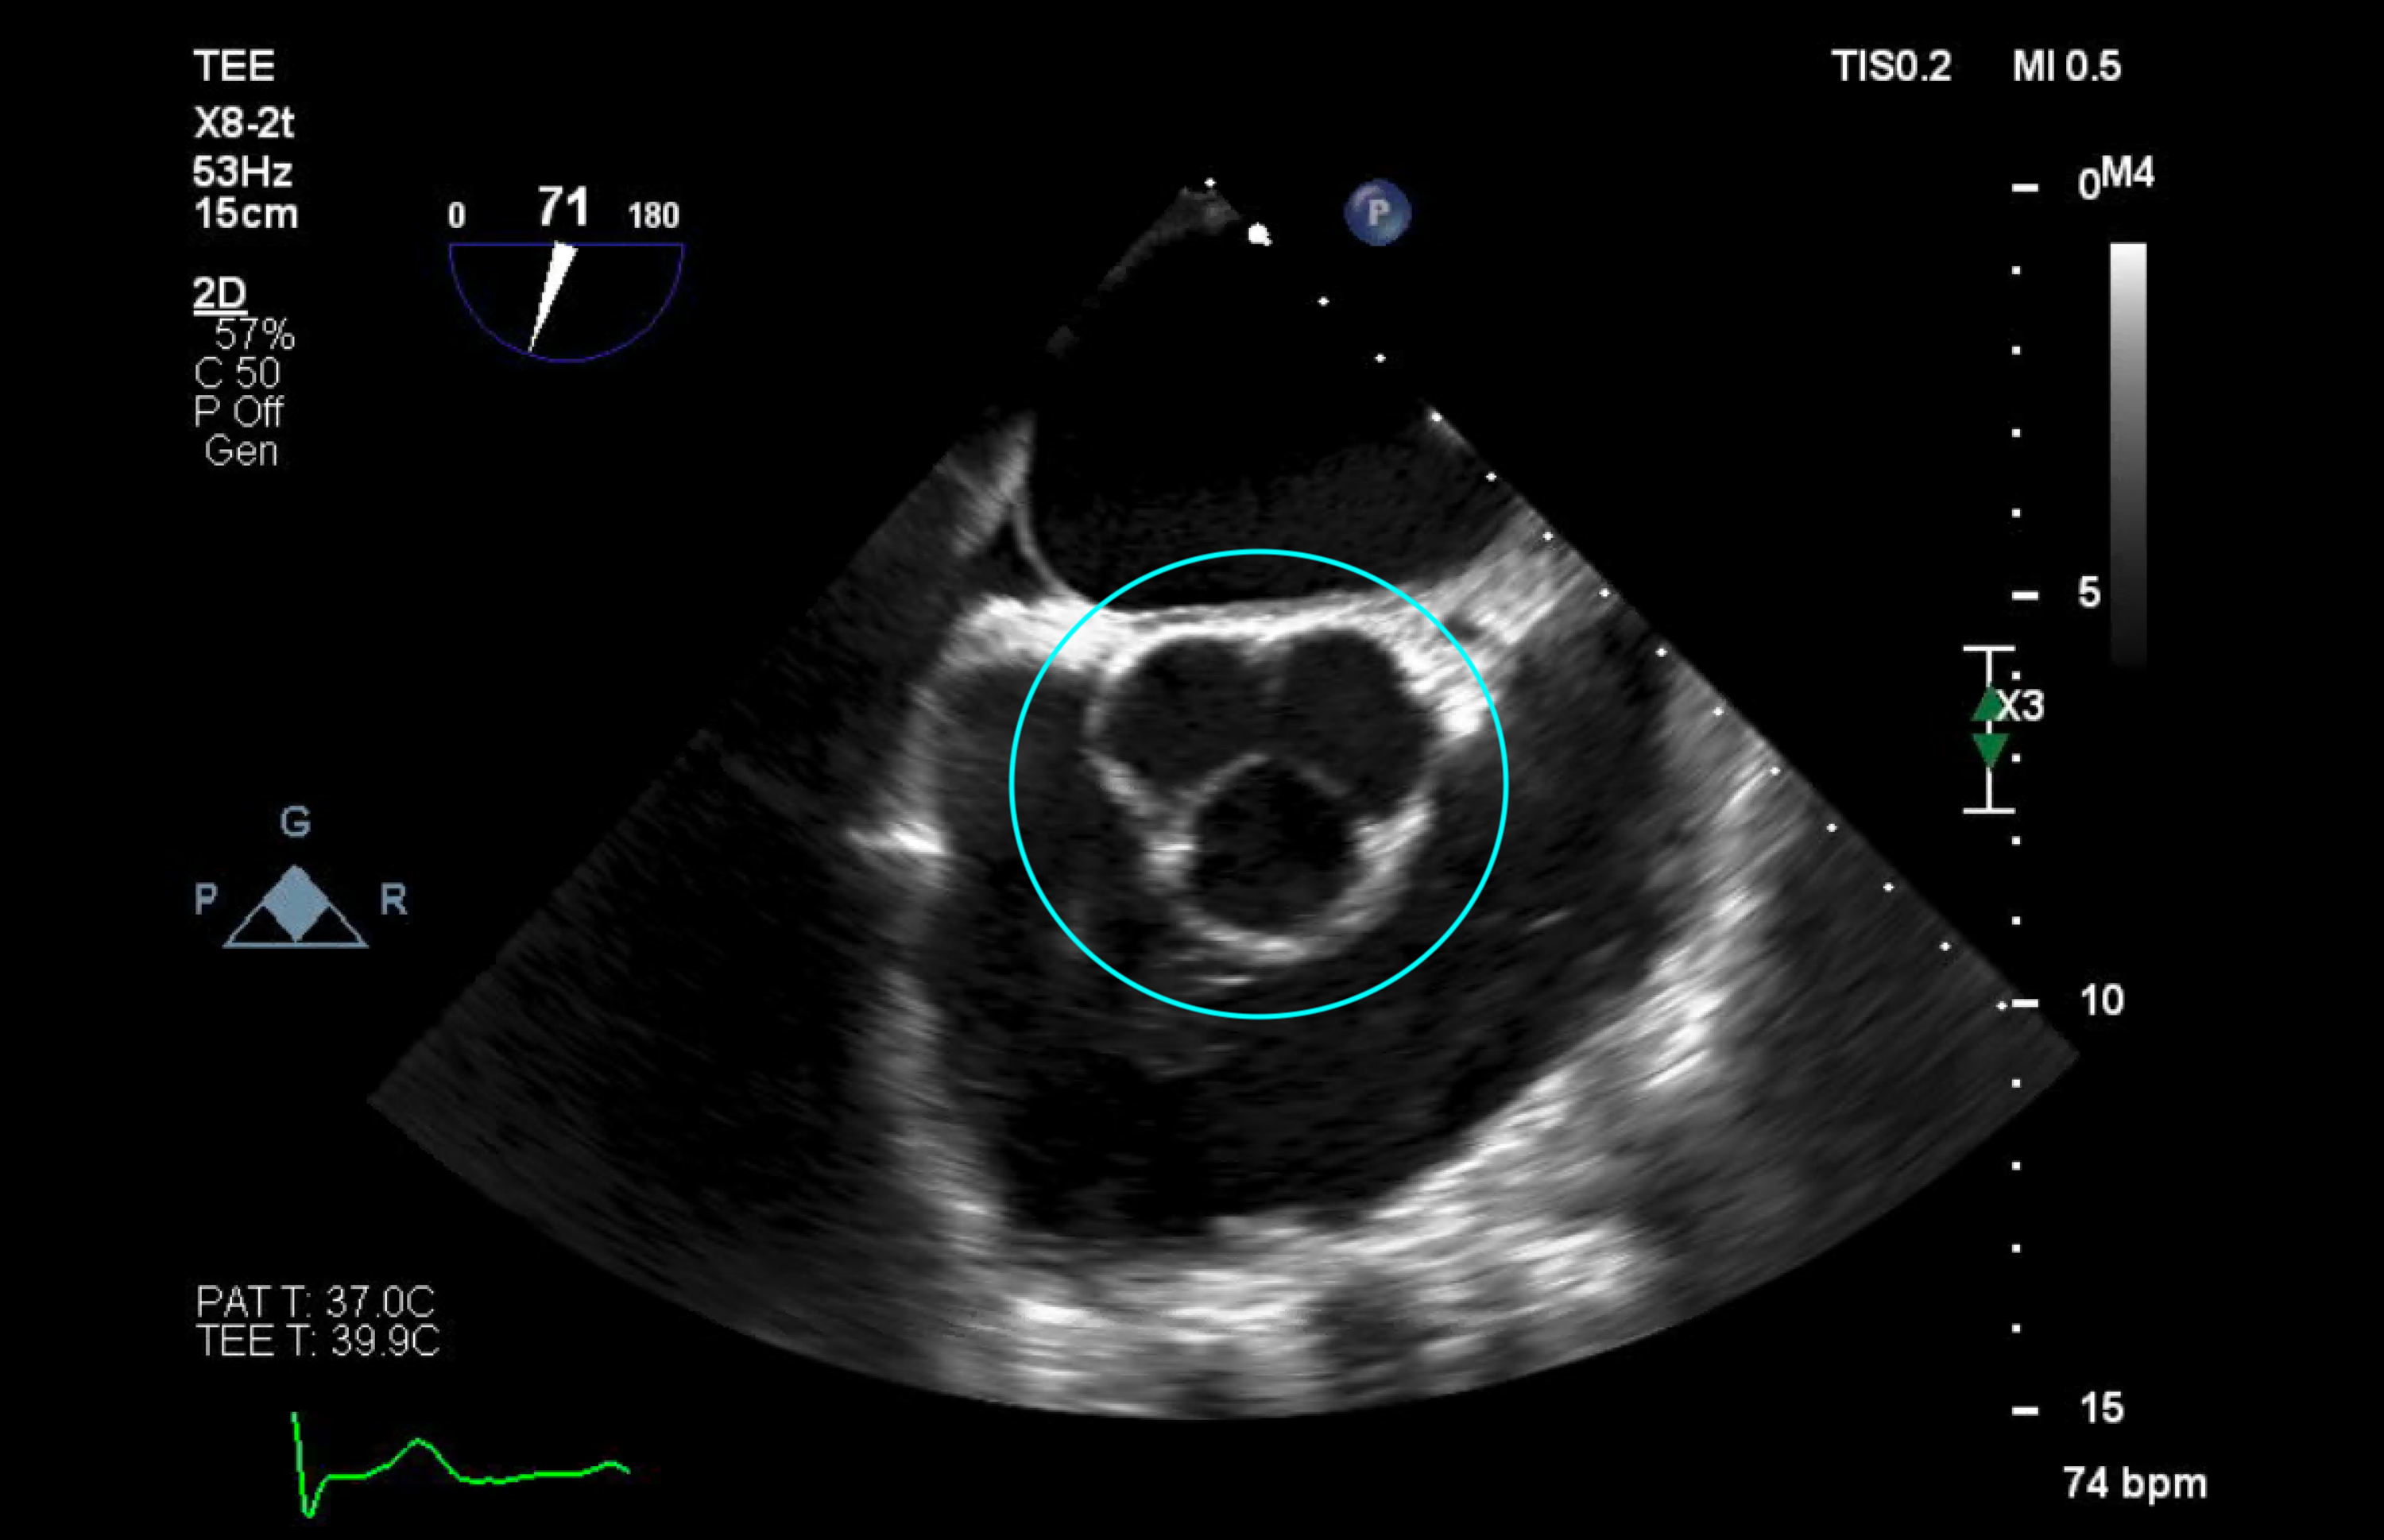

Cureus Staphylococcus capitis Endocarditis of a Native Valve

Staphylococcus aureus infective endocarditis role of transoesophageal Staph Infection Heart Valve Review the appropriate evaluation skills required to assess suspected cases of infective endocarditis. Clinical observations suggest that staphylococcus aureus infects either damaged or inflamed heart valves. Infective endocarditis is an infection caused by bacteria that enter the bloodstream and settle in the heart lining, a heart valve or a blood vessel. Endocarditis, most often from a bacterial infection, inflames the. Staph Infection Heart Valve.

Figure 1 from Staphylococcus caprae native mitral valve infective Staph Infection Heart Valve Endocarditis, most often from a bacterial infection, inflames the lining of your heart valves and chambers. Treatment includes several weeks of. Bacterial endocarditis is an infection of the heart’s inner lining or heart valves. Infective endocarditis is a rare bacterial infection affecting your heart valves. It can damage or destroy the heart valves and lead to complications such as stroke. Staph Infection Heart Valve.

Cureus Staphylococcus capitis Endocarditis of a Native Valve Staph Infection Heart Valve Staph bacteria can also damage the heart valves and lead to heart failure. Review the appropriate evaluation skills required to assess suspected cases of infective endocarditis. Summarize the etiology of infective endocarditis. It can damage or destroy the heart valves and lead to complications such as stroke or heart failure. Treatment includes several weeks of. It's a serious condition that. Staph Infection Heart Valve.